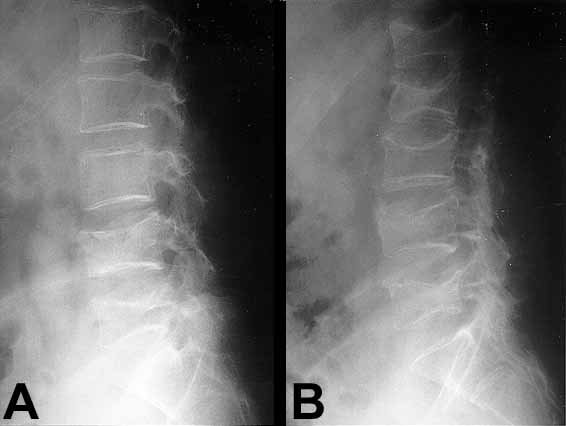

Figura 1A.. Rx simple Columna vertebral Figura 1B.Ocho meses después.

Figura 2.Aplastamientos vertebrales L4-L5.